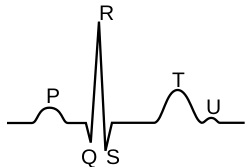

The ECG

E.C.G stands for Electrocardiogram and represents the electrophysiology of the heart. Cardiac electrophysiology is the science of the mechanisms, functions, and performance of the electrical activities of specific regions of the heart. The ECG is the recording of the heart's electrical activity as a graph. The graph can show the heart's rate and rhythm, it can detect enlargement of the heart, decreased blood flow, or the presence of current or past heart attacks. ECG's are inexpensive, Non-invasive, quick, and painless. Depending on the results, the patient’s medical history, and a physical exam; further tests or a combination of medications and lifestyle changes may be ordered.

Electrocardiogram

• The P is the atrial depolarization

• QRS is the ventricular depolarization, as well as atrial repolarization.

• T is the ventricular repolarization

5. When reading an EKG, this letter shows the depolarization from the AV node down to the AV bundle

- A) S

- B) P

- C) U

- D) T

- E) Q

6. The T wave in an EKG shows

- A) Resting potential

- B) Atrial depolarization

- C) SA node excitation

- D) Ventricle repolarization

- E) Purkinje Excitation